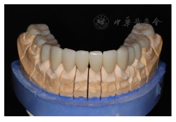

架临时修复体患者戴用无不适,上颌牙制作永久修复体,戴牙(图32,图33)。同样,对下颌牙进行牙体预备,取模,制作永久修复体,戴牙(图34,图35,图36,图37,图38,图39)。

最后的修复体使用预烧结的超透氧化锆(DD cubeX2 98 color,Dental Direkt,德国)制作,为了增强

贴面粘接,组织面喷涂硅涂层(LiSi Connect,爱迪特,中国),烧结,完成粘接,调